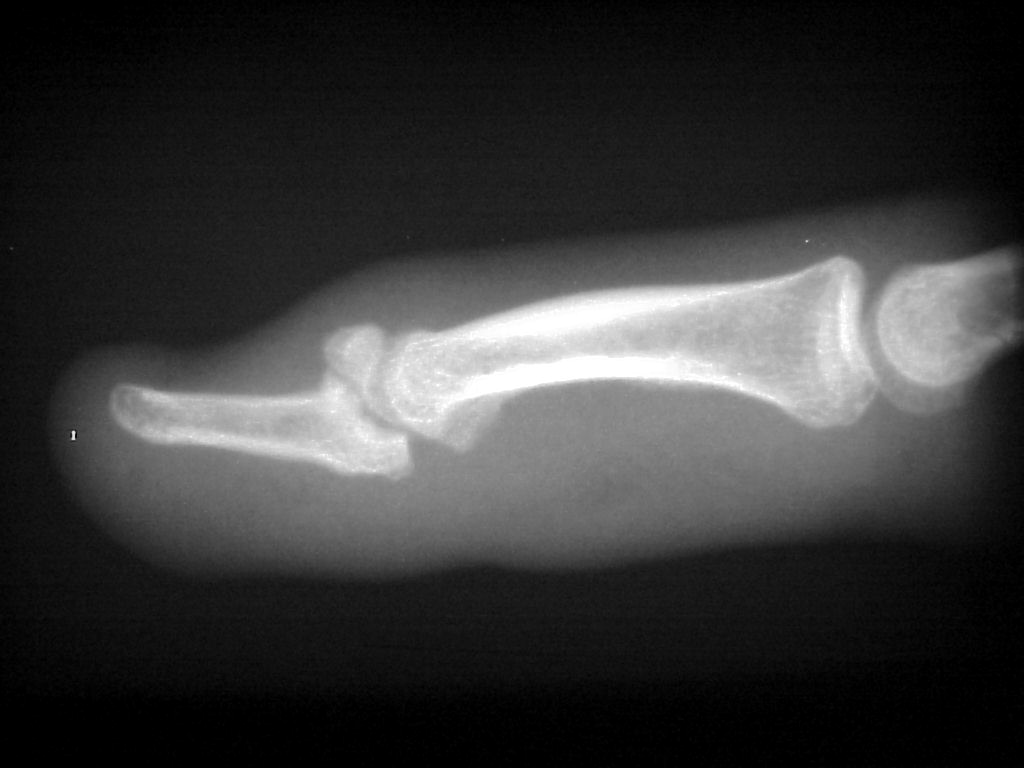

Clinical Example: Mallet fingers

mallet finger